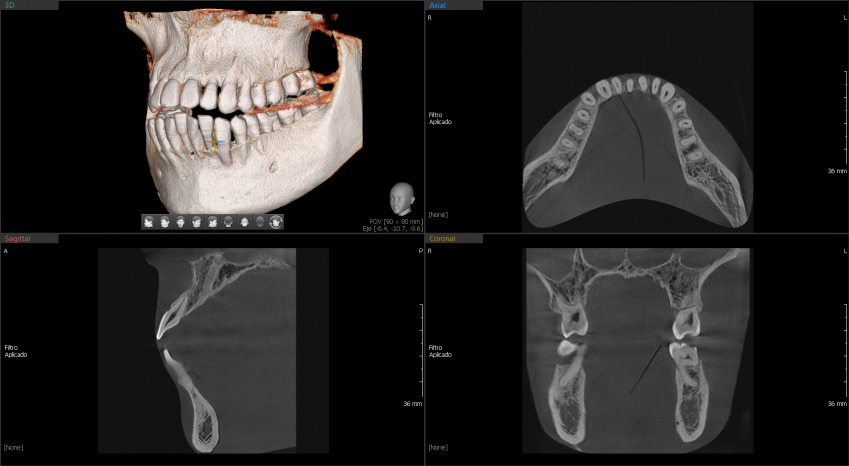

A9 cuenta con una tecnología lite que además de la función PANO + CEPH te permite obtener imágenes CT de manera lite para tu diagnóstico. Proporciona las imágenes más precisas y de mayor calidad.

Las imágenes 3D permiten realizar diagnósticos precisos para planificar los tratamientos dentales. Incluye la áreas maxilar y mandibular en una sola exposición. Ideal para cirugías de implantes y diagnósticos en cirugía oral.